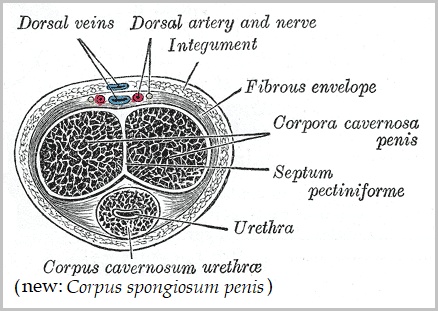

Definition of corpus spongiosum NCI Dictionary of Cancer Terms NCI on sale, Corpus spongiosum penis Wikipedia on sale, Corpus spongiosum penis anatomy Britannica on sale, Corpus cavernosum penis Wikipedia on sale, Corpus Spongiosum of Penis Right Half Complete Anatomy on sale, Corpus spongiosum penis anatomy Britannica on sale, What is the Difference Between Corpus Cavernosum and Corpus on sale, Anatomy corpora cavernosa and spongiosum note the rather large on sale, Corpus Spongiosum StoryMD on sale, Corpus spongiosum penis Wikipedia on sale, Penis Brandywine Urology Consultants on sale, The Penis Structure Muscles Innervation TeachMeAnatomy on sale, SEER Training Penis on sale, Corpus Spongiosum of Penis Left Half Complete Anatomy on sale, Corpus spongiosum penis on sale, Corpus spongiosum Location Functions and Pictures Bodterms on sale, Corpus spongiosum of penis e Anatomy IMAIOS on sale, 3d rendered medically accurate illustration of the corpus on sale, Corpus Spongiosum of Penis Left Half Complete Anatomy on sale, Corpus Spongiosum 6 by Sebastian Kaulitzki science Photo Library on sale, How to identify priapism Medmastery on sale, Penis Anatomy Histology Histology Flashcards ditki medical on sale, Penis Radiology Reference Article Radiopaedia on sale, Corpus spongiosum Location Function Problems and Pictures on sale, Corpus spongiosum hi res stock photography and images Alamy on sale, Hypothesis that urethral bulb corpus spongiosum plays an active on sale, Corpus spongiosum is a part ofA. OvaryB. TestisC. UterusD. Male on sale, Normal penile anatomy. a Drawing axial view illustrates the on sale, 64 Corpus Spongiosum Royalty Free Photos and Stock Images on sale, Symptomatic corpus spongiosum defect in adolescents and young on sale, Corpus Spongiosum 10 by Sebastian Kaulitzki science Photo Library on sale, Corpus Spongiosum Penis Anatomy Function Diagram Body Maps on sale, urethra and corpus spongiosum Histologia on sale, Corpus cavernosum penis Wikipedia on sale, Tissue 177 Penile Urethra and Corpus Spongiosum on sale.

Definition of corpus spongiosum NCI Dictionary of Cancer Terms NCI on sale, Corpus spongiosum penis Wikipedia on sale, Corpus spongiosum penis anatomy Britannica on sale, Corpus cavernosum penis Wikipedia on sale, Corpus Spongiosum of Penis Right Half Complete Anatomy on sale, Corpus spongiosum penis anatomy Britannica on sale, What is the Difference Between Corpus Cavernosum and Corpus on sale, Anatomy corpora cavernosa and spongiosum note the rather large on sale, Corpus Spongiosum StoryMD on sale, Corpus spongiosum penis Wikipedia on sale, Penis Brandywine Urology Consultants on sale, The Penis Structure Muscles Innervation TeachMeAnatomy on sale, SEER Training Penis on sale, Corpus Spongiosum of Penis Left Half Complete Anatomy on sale, Corpus spongiosum penis on sale, Corpus spongiosum Location Functions and Pictures Bodterms on sale, Corpus spongiosum of penis e Anatomy IMAIOS on sale, 3d rendered medically accurate illustration of the corpus on sale, Corpus Spongiosum of Penis Left Half Complete Anatomy on sale, Corpus Spongiosum 6 by Sebastian Kaulitzki science Photo Library on sale, How to identify priapism Medmastery on sale, Penis Anatomy Histology Histology Flashcards ditki medical on sale, Penis Radiology Reference Article Radiopaedia on sale, Corpus spongiosum Location Function Problems and Pictures on sale, Corpus spongiosum hi res stock photography and images Alamy on sale, Hypothesis that urethral bulb corpus spongiosum plays an active on sale, Corpus spongiosum is a part ofA. OvaryB. TestisC. UterusD. Male on sale, Normal penile anatomy. a Drawing axial view illustrates the on sale, 64 Corpus Spongiosum Royalty Free Photos and Stock Images on sale, Symptomatic corpus spongiosum defect in adolescents and young on sale, Corpus Spongiosum 10 by Sebastian Kaulitzki science Photo Library on sale, Corpus Spongiosum Penis Anatomy Function Diagram Body Maps on sale, urethra and corpus spongiosum Histologia on sale, Corpus cavernosum penis Wikipedia on sale, Tissue 177 Penile Urethra and Corpus Spongiosum on sale.